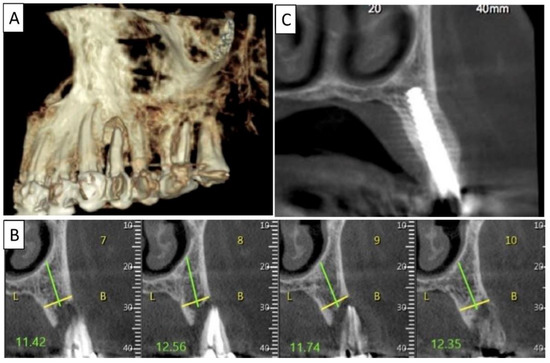

Figure 3.

(A) Lateral volumetric cone beam computed tomography (CBCT) shows significant loss of buccal and palatal bone mass around tooth 24. (B) Coronal CBCT slice of the same area of tooth 24 revealing missed buccal and palatal bone and associated apical radiolucency. (C) The coronal CBCT section shows the implant in the area of tooth 24 and the obtained completely regenerated cortical and palatal plates.

The patient was a 65-year-old female in good general health condition. The patient presented with tooth 24, root canal treatment, post, core build up, and an old porcelain-fused-to-metal (PFM) crown. A vertical root fracture was present with an associated severe bone loss, including loss of both buccal and palatal plates.

The non-traumatic extraction of tooth 24. was performed, (Figure 2). The magnesium membrane shield technique was performed as described in Section 2, aiming to rebuild both buccal and palatal plates. In this instance, the magnesium membrane was used as a single layer on both the buccal and palatal sides.

Figure 2.

(A) Alveolar socket following atraumatic extraction and curettage. Severe bone loss of both buccal and palatal plates. (B) Buccal and palatial plates were created using the magnesium membrane shield technique. (C) Application of allograft. (D) Four months post operatively there was an excellent regeneration of bone defect, including fully regenerated cortical and palatal plates. The implant was stable and there was a good healing of the soft tissues. Black arrows are used to indicate the position of the magnesium membrane.

Four months post operatively, regenerated bone was present, including fully regenerated cortical and palatal plates (Figure 3). The implant was stable and there was a good healing of the soft tissues.